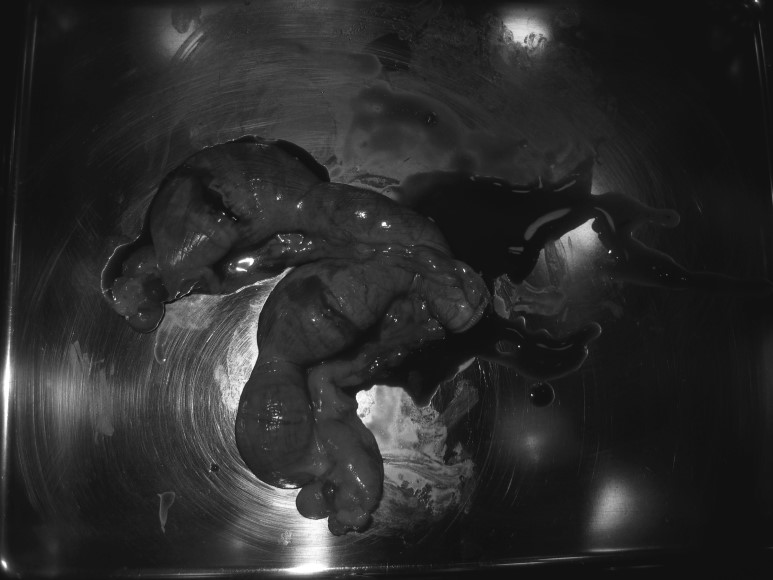

수술 후 제거한 자궁을 깨뜨렸더니 피고름이 자궁을 가득 채우고 있었습니다.자궁축농증은 적절한 치료 시기를 놓치면 패혈증이 되어 수술 중이거나 수술 후에도 위험할 수 있습니다.외음부에 분비물이 있거나 배가 부르면 반드시 진찰을 받아 주시기 바랍니다.모든 사진은 환자분의 수술 중에 보호자 설명을 위해 스스로 찍은 사진입니다. 사진보다 치료가 먼저이므로 사진이 부족해서 완벽하지 않을 수 있습니다.2차병원 주치의가 야탑데 야탑딜리동물병원 www.dilly.co.kr 월~토 AM10:00~PM8:00 일요일 AM10:00~PM6:00 런치타임 12:00~13:00 Tel 031.605.1275 경기도 성남시 분당구 성남대로 884-9 라비앙 오피스텔